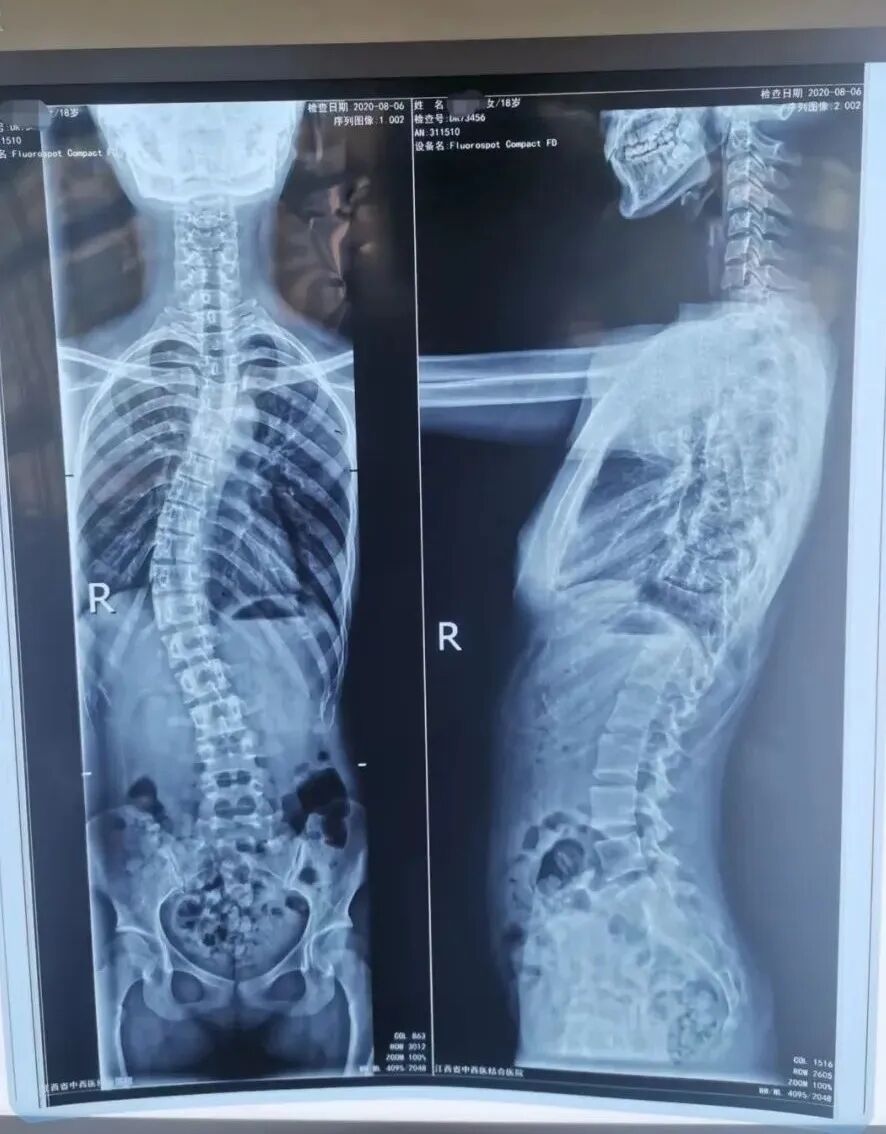

万一怀疑孩子有问题,一定要到医院进行专业的脊柱侧弯筛查,目前诊断脊柱侧弯的金标准是站立位拍脊柱全长X线片正侧位。

我们要做的,就是在明白疾病自然进程的前提下积极对症干预,生长发育只有一次,抓住黄金矫正期。

矫正前 Vs. 矫正后

前后对比